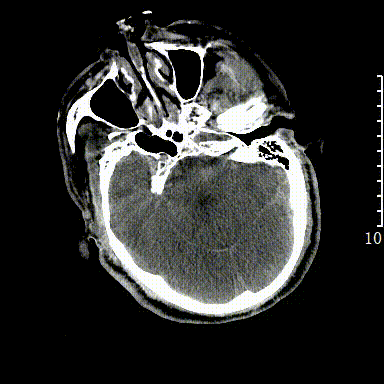

CT

rCBF<30%:25.1ml

Tmax>6.0s:173.9ml

失配体积:148.8ml

1、急性脑梗死。2、左侧大脑中动脉M1段闭塞。